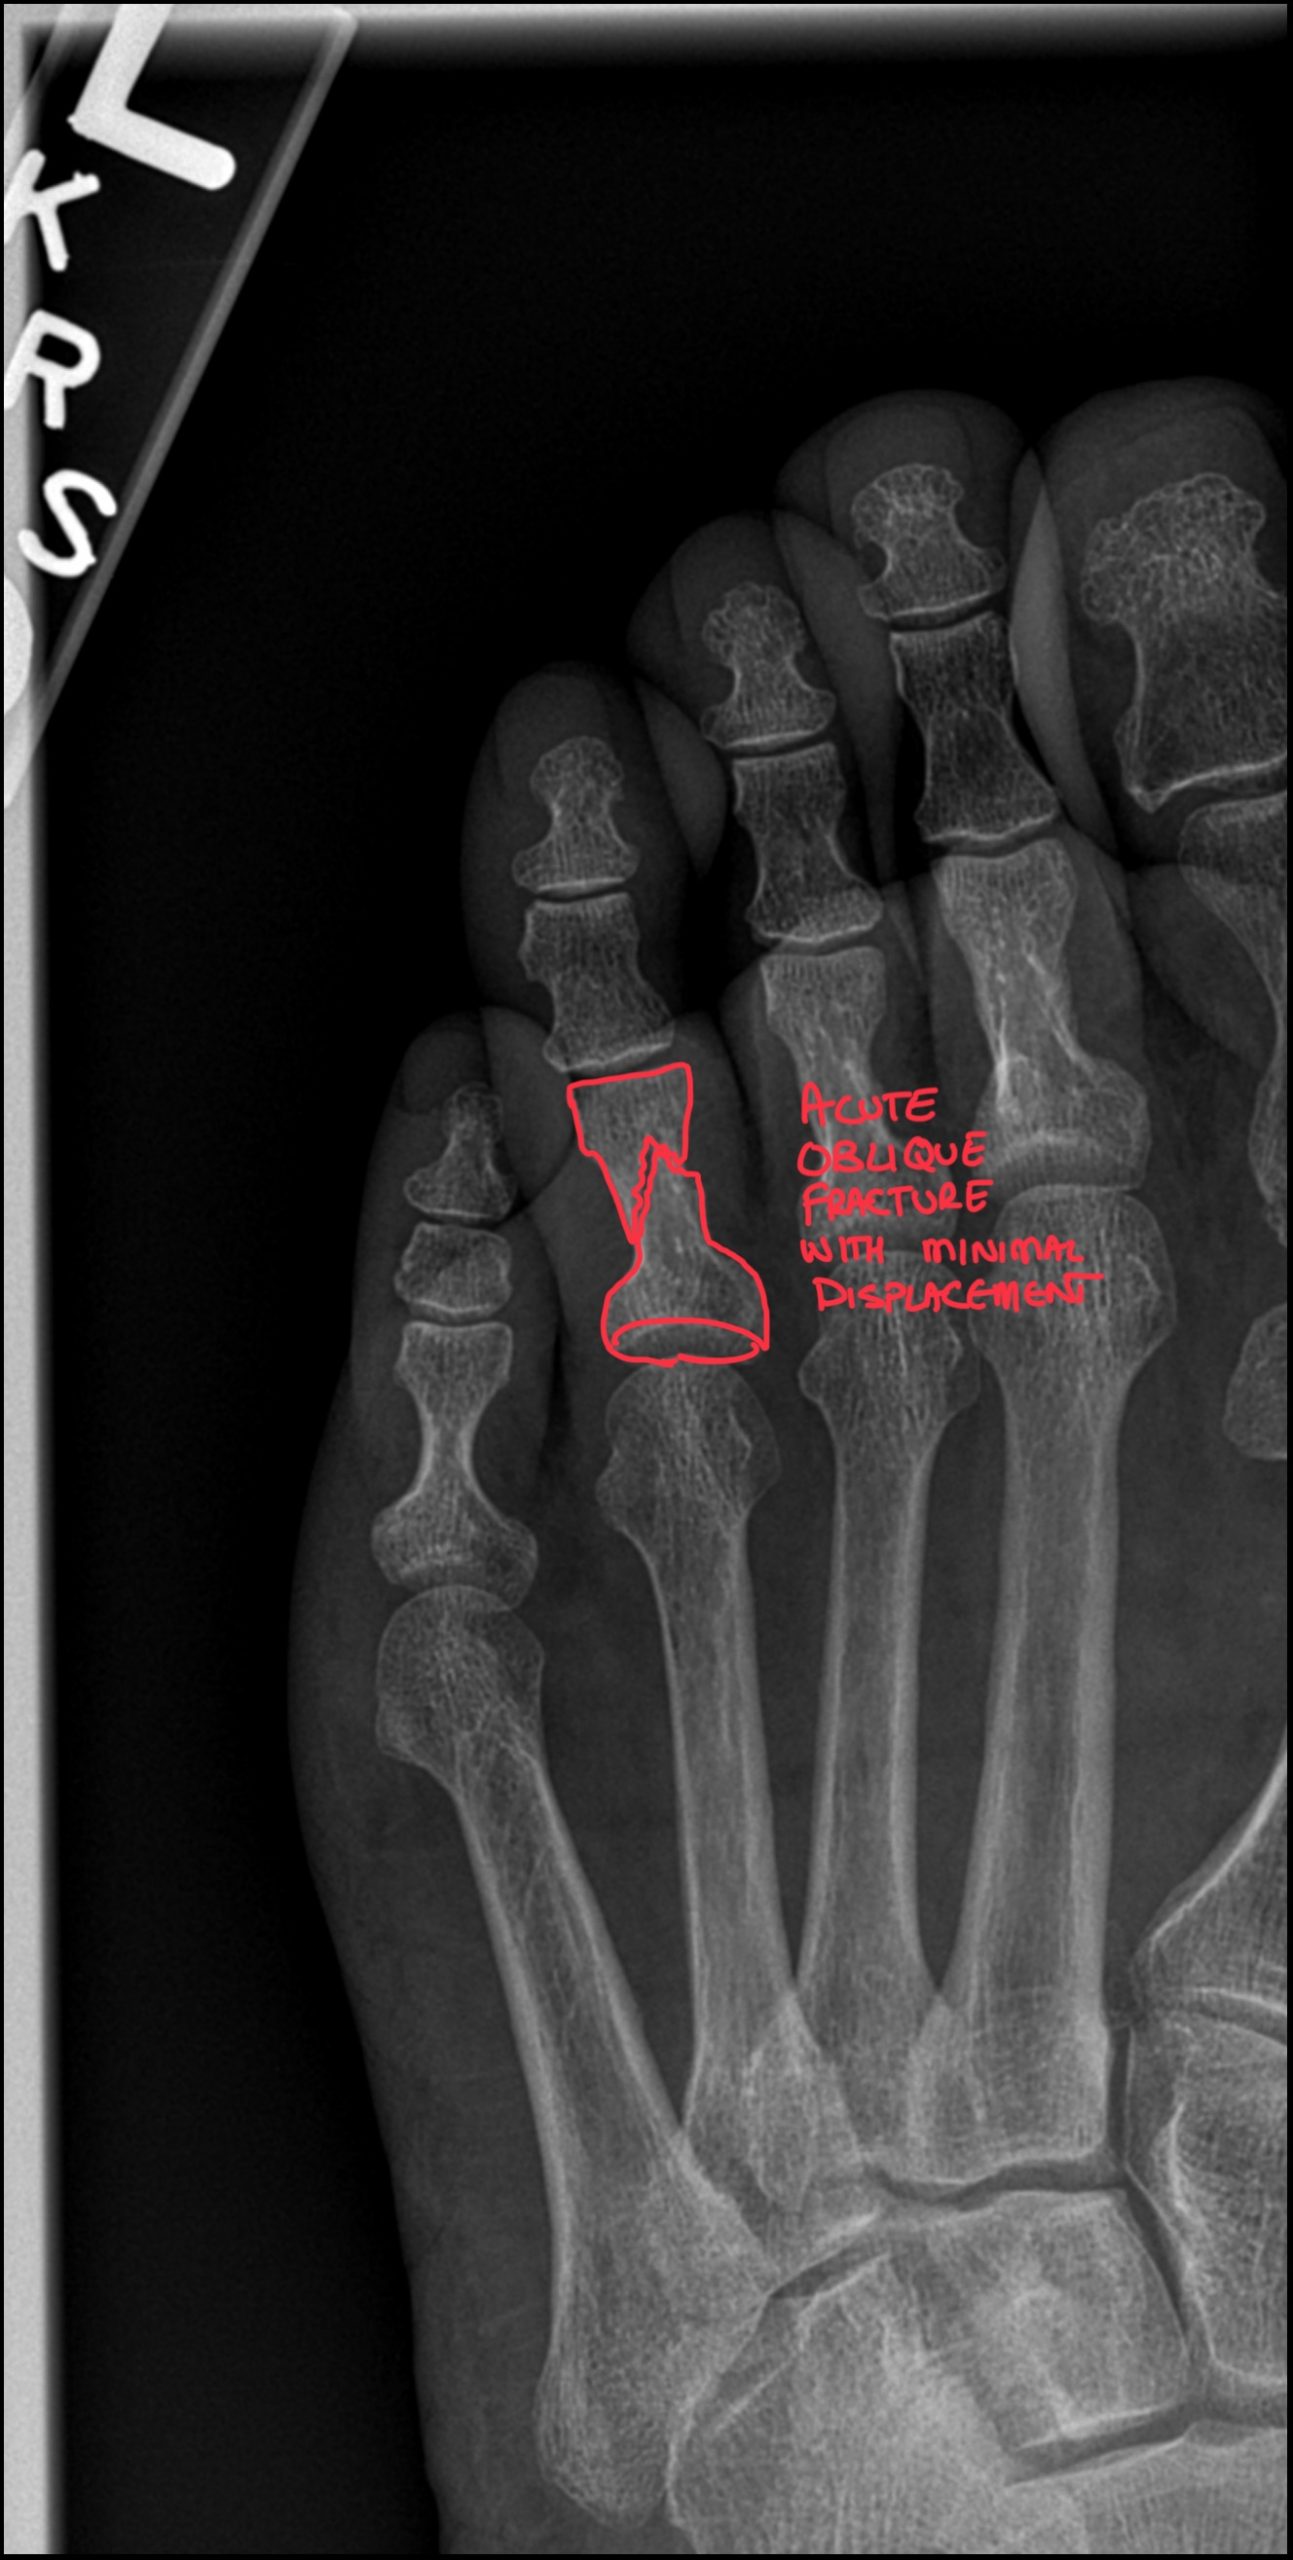

Second Metatarsal Stress Fracture: Diagnostic Imaging Consultants Guide to X-ray and MRI Findings

Second Metatarsal Stress Fracture: Diagnostic Imaging Consultants Guide to X-ray and MRI Findings Key Takeaways The “Silent” Fracture: Stress fractures

Read More